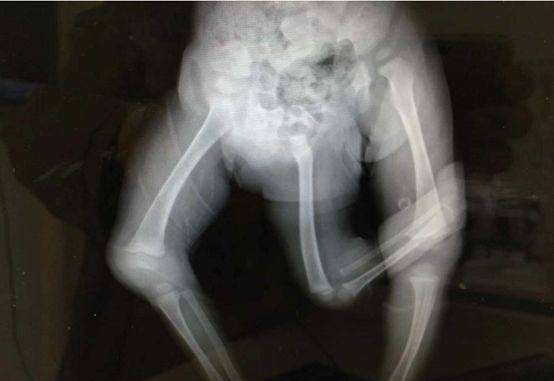

图片说明:影像学检查资料。图片由陈秋医生提供。